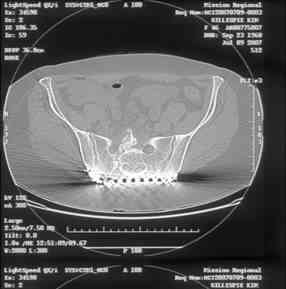

I can't see the axial CT images well enough to detail the potential sacral issues....can you magnify them?

Here is a magnified view. Sorry about the quality but the CT was scanned into our system.

Thank you...it might help to remove the disengaged and other iliosacral screws then insert longer lag screws into the upper sacral segment and if anatomically feasible into the second sacral segment as well.

You could do it percutaneously and even add an electrical stimulation device if that seems reasonable.